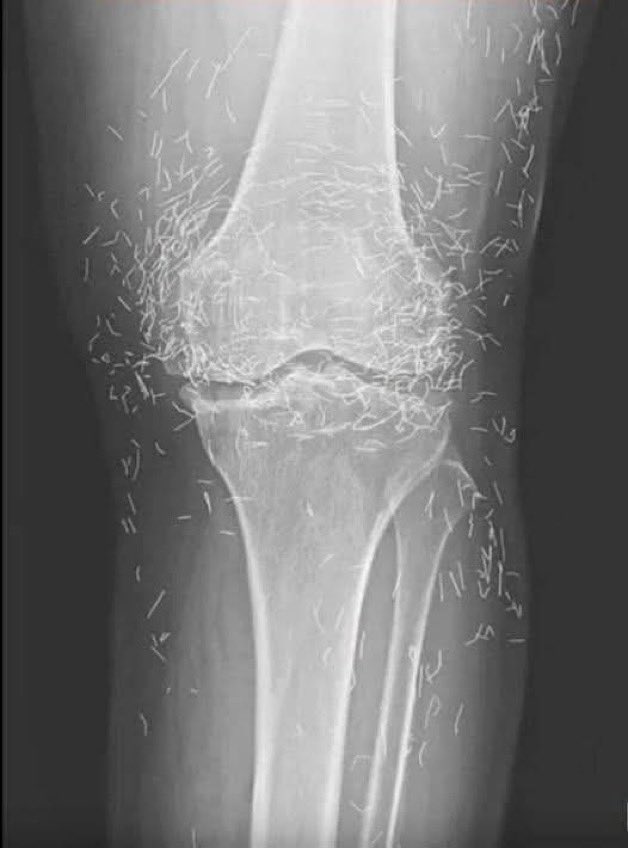

The patient visited the hospital complaining of severe knee pain, swelling, and limited range of motion. This is an X-ray of the affected area to determine the cause. What is shown in the image? @grok What is the diagnosis?